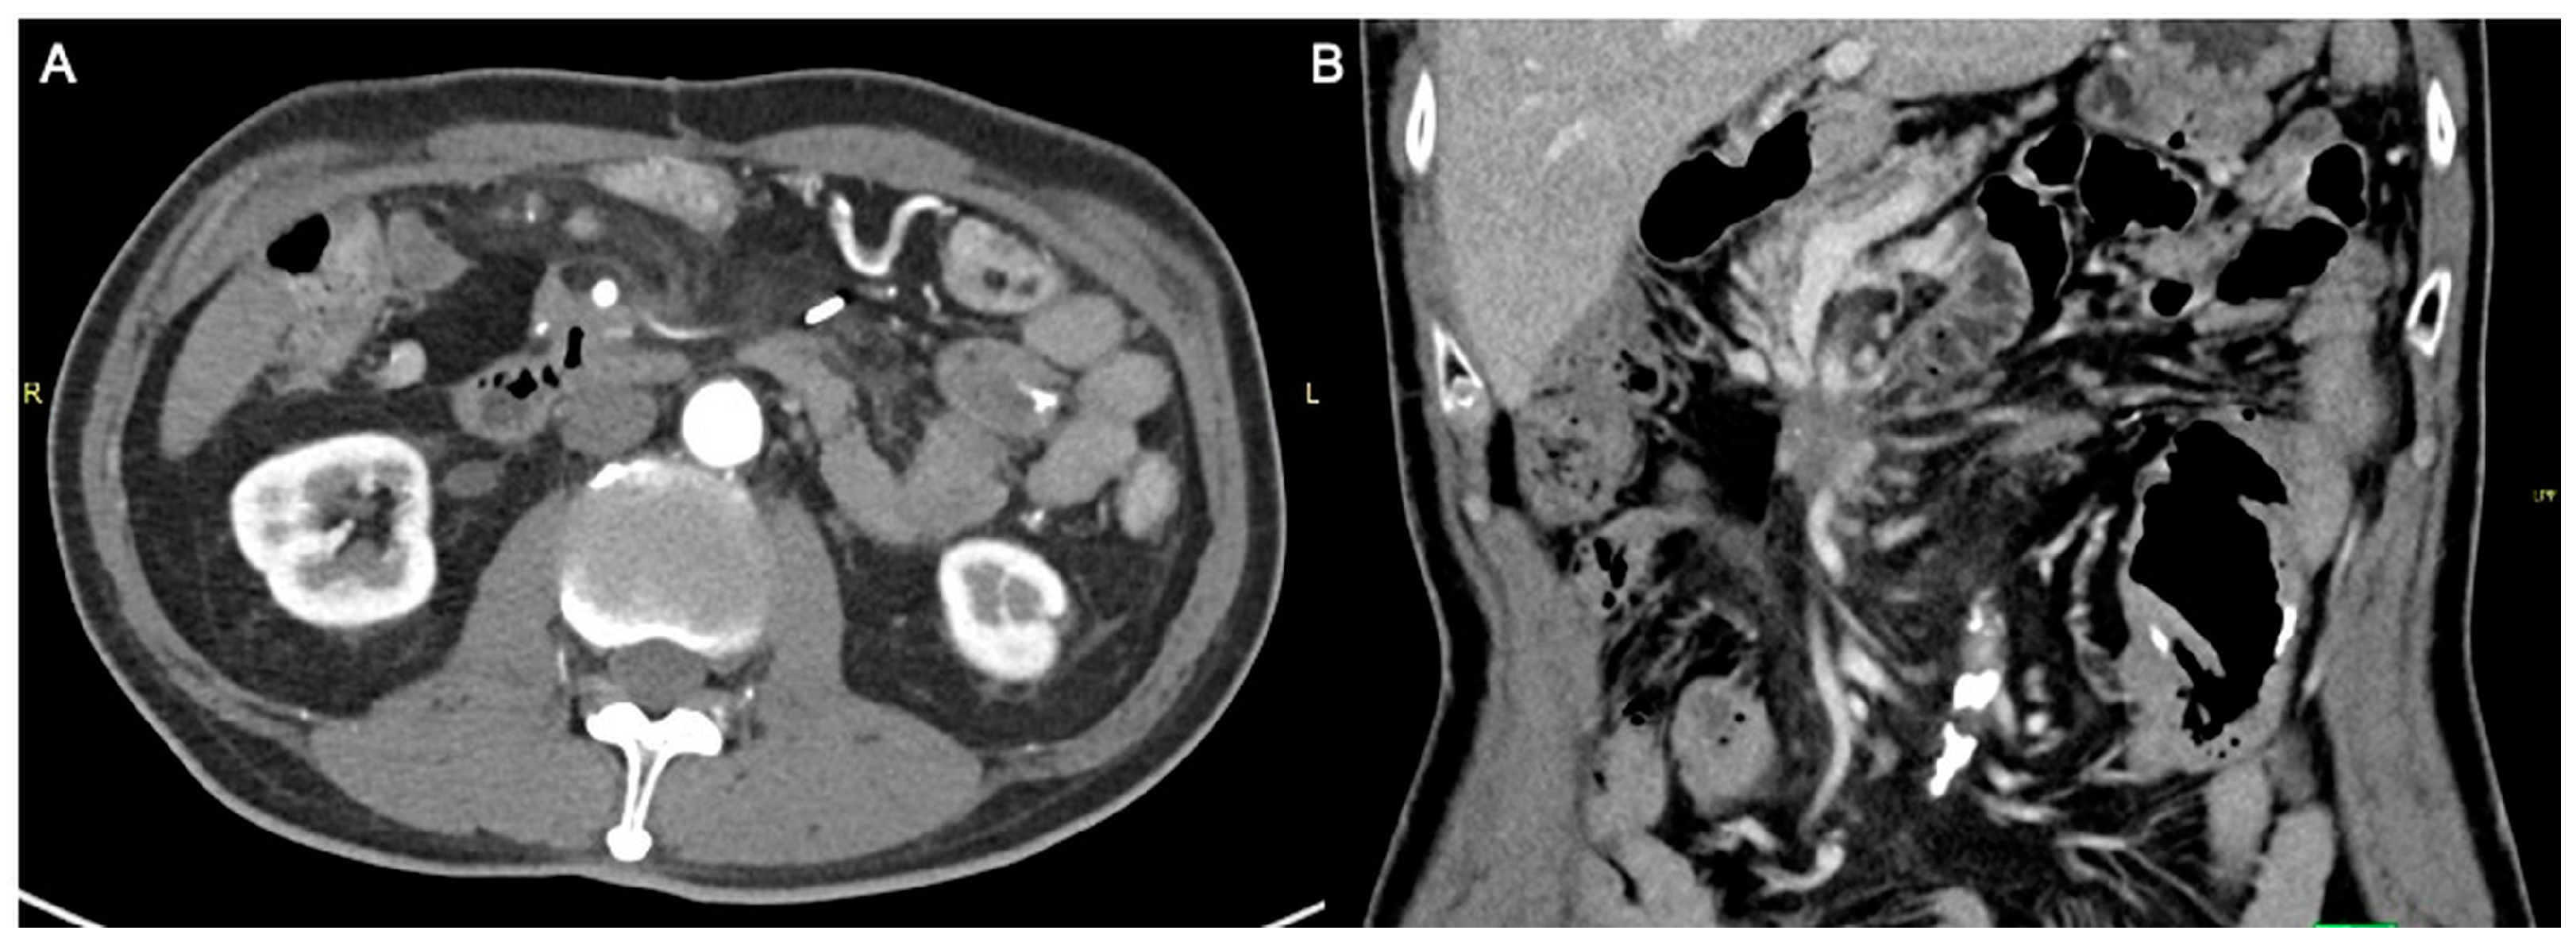

A 59-year-old man with an Eastern Cooperative Oncology Group (ECOG) performance status of 0 presented with LAPC of the uncinate process (biopsy proven pancreatic neuroendocrine carcinoma) with duodenal invasion (Figure 1A,B). The patient underwent a combination of chemotherapy and radiation therapy but was found to have stable disease.

Figure 1.

Axial (A) and coronal (B) computed tomography images of the patient demonstrating a heterogeneously enhancing pancreatic mass measuring approximately 6.3 × 4.4 cm. There is duodenal involvement by the pancreatic mass (arrows).